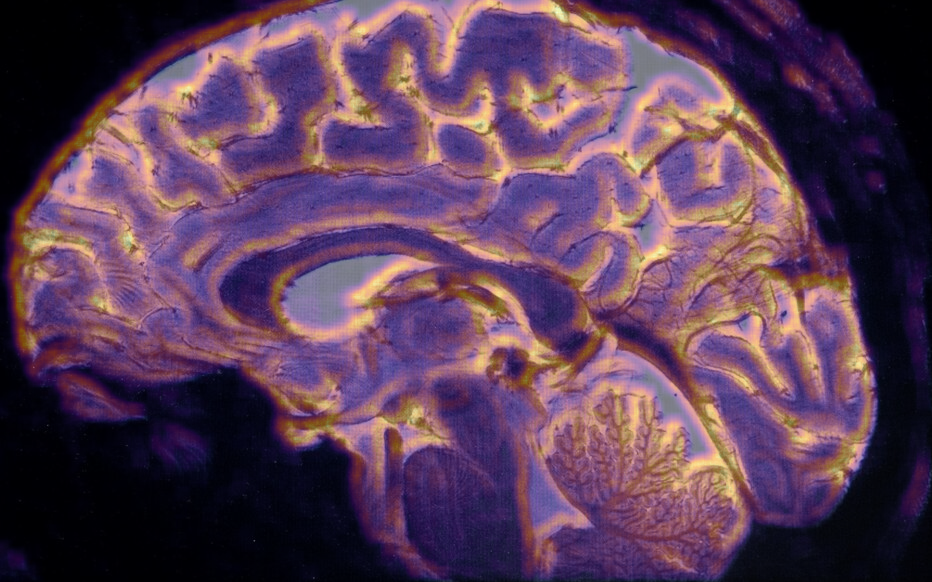

Médical

Voir n’est plus regarder : c’est comprendre la structure du monde cellulaire.

Loin du contraste classique, ϕ explore la richesse interne des tissus.

Elle distingue l’homogène du structuré, le bruit du sens, et redonne au regard médical une dimension topologique : celle de l’information vivante.

Les structures fines, souvent invisibles à l’œil nu, s’y dessinent comme des reliefs entropiques — un paysage du corps, révélé par la mathématique du vivant.